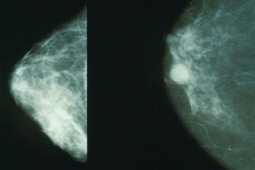

Polska spółka wykorzystująca ciekłokrystaliczną termografię kontaktową w diagnostyce raka piersi...